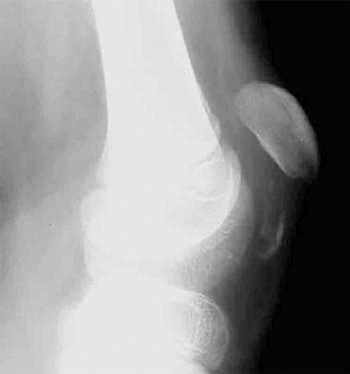

![]() |

Figure 33.15 Radiographic lines of the distal humerus. A:

The Baumann angle is formed between the capitellar physeal line and a line perpendicular to the long axis of the humerus. As this angle becomes smaller, more elbow varus will occur. This angle should be compared with that of the contralateral, uninjured elbow with a similar anteroposterior view of the distal humerus. B: Line A is the anterior humeral line, which atypically passes through the middle of the capitellum. Angle B demonstrates the anterior angulation of the capitellum relative to the humeral shaft. This is approximately 30 degrees. As angle B becomes smaller, the fracture site is moved into extension. Fracture alignment with the capitellum behind the anterior humeral line produces a hyperextension deformity and a loss of elbow flexion. |

There are several helpful radiographic lines and angles that can be

measured to determine if there is adequate postinjury alignment; a

comparison view of the other elbow may be valuable as a reference (Fig. 33.15).

All measurements are subject to the inaccuracies caused by elbow

positioning, and this should be kept in mind when making clinical

decisions. The Baumann angle is used to assess the varus attitude of

the distal humerus, usually after a supracondylar elbow fracture. It is

the angle formed between the capitellar physeal line and a line

perpendicular to the long axis of the humerus. This angle normally

should be within 5 to 8 degrees of the same angle in the contralateral

elbow. An anteroposterior view of the distal humerus, positioned

parallel to the radiographic plate, is necessary to reduce the

variation of the Baumann angle that occurs when the arm is rotated. Ten

degrees of rotation produces a 6-degree change in the angle (124).

Another measure of coronal alignment is the medial epicondylar

epiphyseal angle. This angle is measured between the long axis of the

humerus and a line through the medial epicondylar physis (125).

It has the advantage of being reliably measured while the elbow is held

in flexion (i.e., Jones view), as during the reduction process. The

medial epicondylar epiphyseal line ranges from 25 to 46 degrees. This

angle is not reliable for children younger than 3 years or older than

10 (125). Sagittal alignment may be determined

by the lateral capitellar angle, which indicates the normal

forward-flexed position of the capitellum. This angle averages 30 to 40

degrees. The anterior humeral line offers a similar means to assess the

position of the capitellum and is measured on a true lateral

radiographic projection. A line along the anterior humeral cortex

should pass through the center of the capitellum.